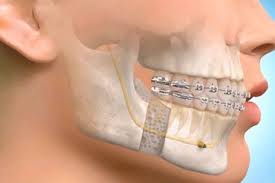

Orthognathic Surgeries

Orthognathic surgery involves the surgical correction of jaw irregularities and is often indicated for patients with significant dental or facial discrepancies. These surgeries may be referred due to:

- Complexity: Orthognathic surgeries are intricate procedures that typically require the expertise of oral and maxillofacial surgeons.

- Pre-Surgical Orthodontics: Patients often need orthodontic treatment prior to surgery to ensure proper alignment, necessitating coordination between orthodontists and surgeons.

Given the complexity of these cases, referrals are essential for optimal surgical outcomes and coordinated patient management, ensuring that patients receive the appropriate orthognathic surgery Dental Services.